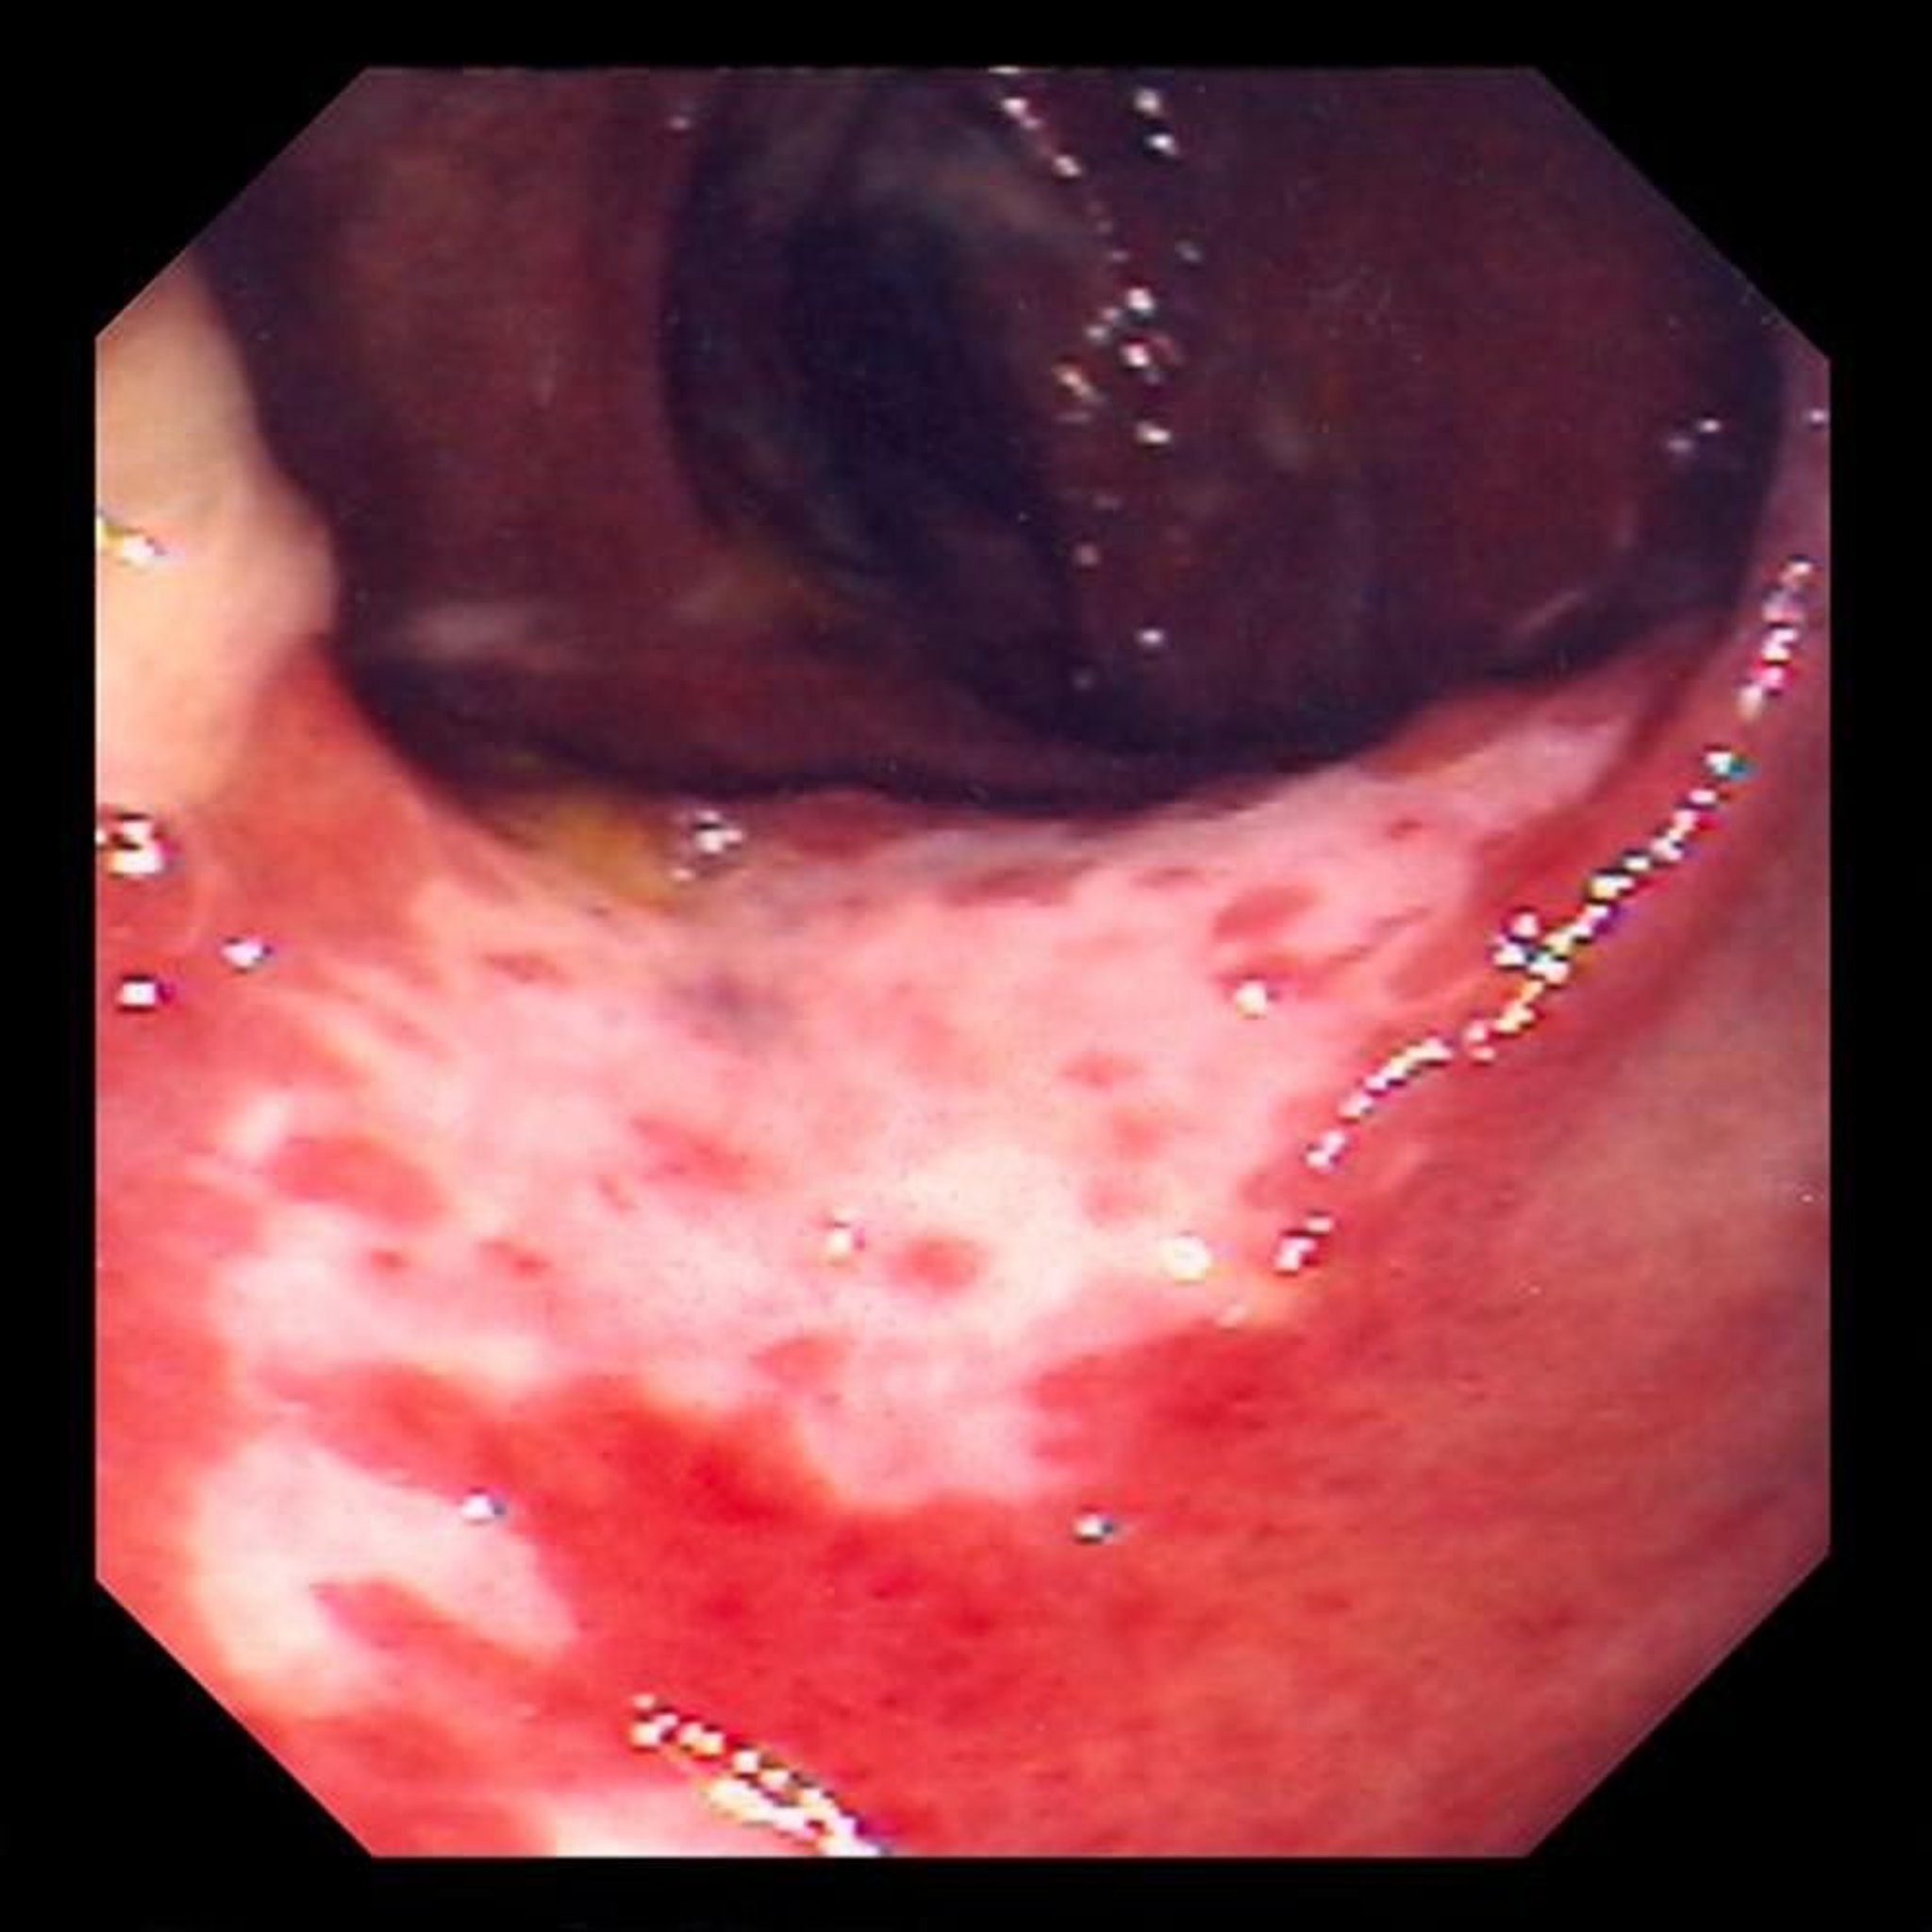

Colitis isquémica (colonoscopia)

Esta foto muestra daños en la mucosa intestinal causados por la obstrucción del flujo sanguíneo. La mucosa intestinal es de color rojo y está cubierta de úlceras (las áreas blancas).

Foto proporcionada por David M. Martin, MD.